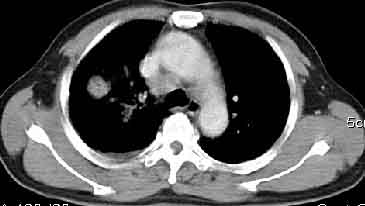

该病例我的诊断意见:右肺上叶周围型肺癌伴纵隔和右肺门淋巴结增大和右肺上叶阻塞性肺炎{病灶周围致密影以近肺门侧明显!}。右侧少量胸腔积液。

一. 1)症状有无发热及慢性过程.2)化验室检查?3)有无tb接触史?二.右肺上叶见片团状影,边界欠清,外侧方见一结节状软组织影,密度欠均匀,内可见低密度坏死区.周围强化明显,肺内见纤维索条影,局部胸膜增厚,但无明确胸膜凹陷.上叶支气管壁增厚,肺门及纵隔淋巴结增大.右侧胸腔少量积液.诊断意见:1右肺上叶慢性感染性疾病(肺tb?)伴肺门,纵隔淋巴结大.右胸少量积液.右肺上叶结节影多为tb球?2右肺上叶周围型肺ca伴肺门,纵隔淋巴结转移待排.右肺上叶炎变(肺门及纵隔淋巴结压迫).右胸少量积液.等待随返结果.

右上肺周围性肺癌,阻塞性肺炎考虑为肿大淋巴结压迫上叶支气管引起。